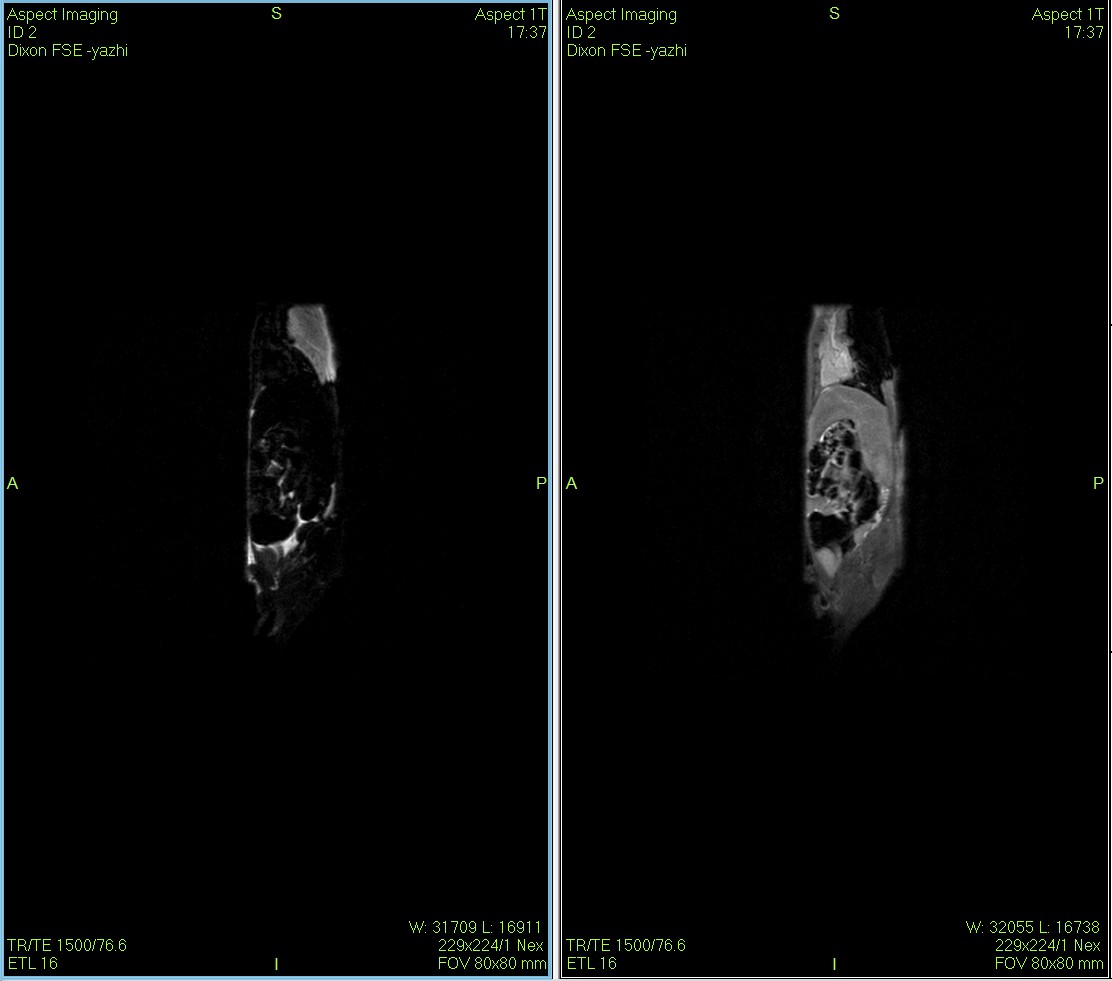

Dixon序列用于大鼠、小鼠水脂分離磁共振成像-脂肪抑制技術

Dixon脂肪抑制技術是由Dixon 提出,其基本原理是利用水、脂肪的化學位移差異,使用不同的回波時問,分別采集水和脂肪質子的in Phase 和 opposed -phase兩種回波信號。